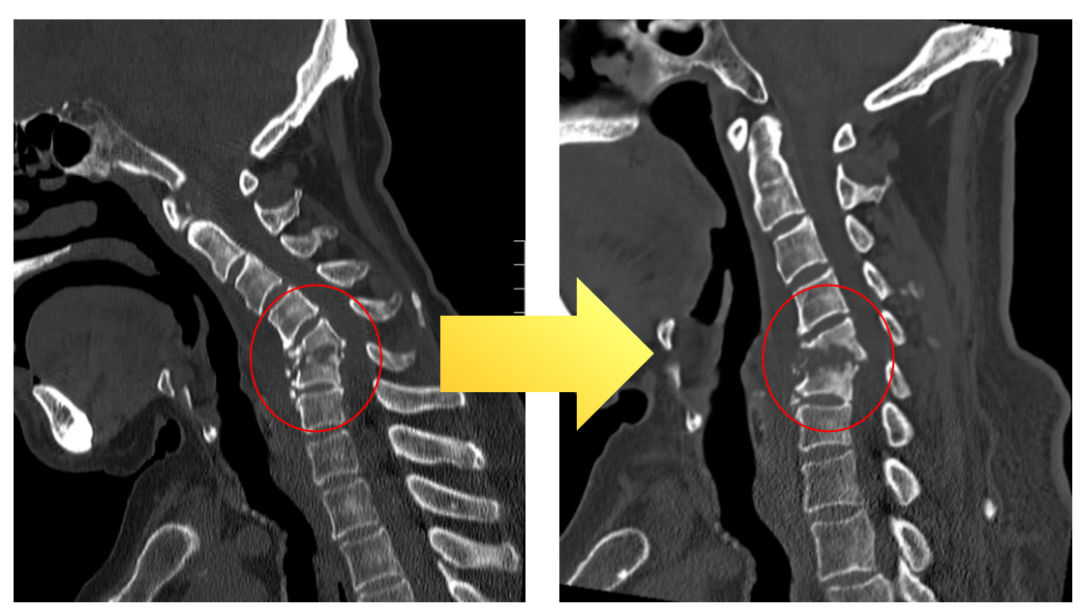

短短半月余时候,刘大爷的C5、C6椎体就被细菌“吃空”,颈椎不稳严重,头颅摇摇欲坠,随时濒临着脊髓压迫导致截瘫的风险!

进一步的CT和磁共振查验揭示了惊心的一幕:刘大爷的C5、C6椎体已被侵蚀松懈,颈椎局部向后凸出变形,周围软组织肿胀。与半个月前的片子对比,病情正在快速恶化。